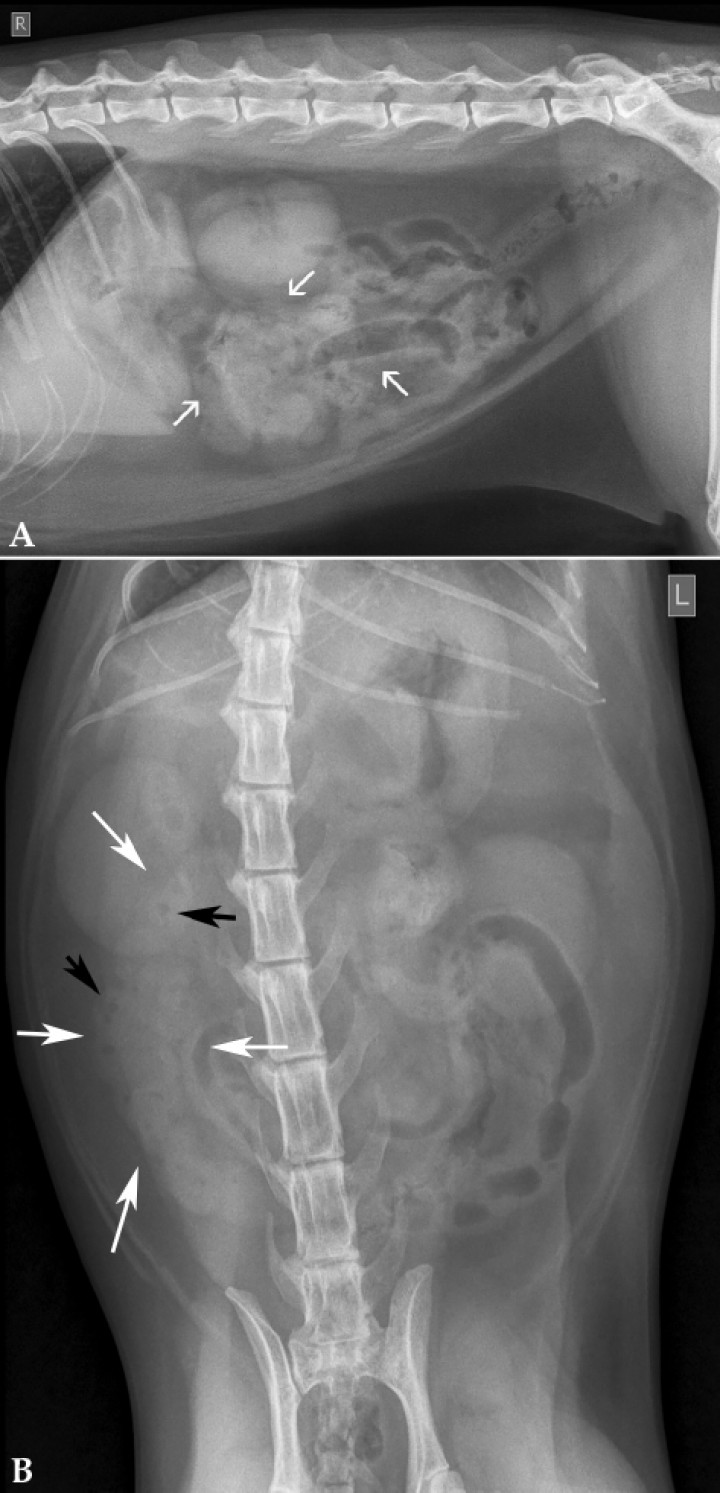

Se observó gran parte de las asas de intestino delgado agrupadas en la zona ventral del abdomen medio (Fig. 2A) y en el lado derecho (Fig. 2B). En su interior se visualizaron pequeñas burbujas de gas distribuidas en forma geométrica. En el resto de las estructuras evaluadas no se apreciaron alteraciones radiológicas evidentes.

<p>Mismas radiografías que en la Figura 1. (<strong>A</strong>) Se observa gran parte de las asas de intestino delgado agrupadas en el abdomen medio (flechas blancas) en la zona ventral. (<strong>B</strong>) Asas agrupadas en el lado derecho (flechas blancas). En su interior se visualizan pequeñas burbujas de gas distribuidas de forma geométrica (flechas negras).</p>

Mismas radiografías que en la Figura 1. (A) Se observa gran parte de las asas de intestino delgado agrupadas en el abdomen medio (flechas blancas) en la zona ventral. (B) Asas agrupadas en el lado derecho (flechas blancas). En su interior se visualizan pequeñas burbujas de gas distribuidas de forma geométrica (flechas negras).

La acumulación de gas de forma anormal en el interior de intestino delgado, con las burbujas adoptando la morfología de un patrón geométrico, es altamente sugestivo de la plicación del intestino delgado compatible con un cuerpo extraño lineal.